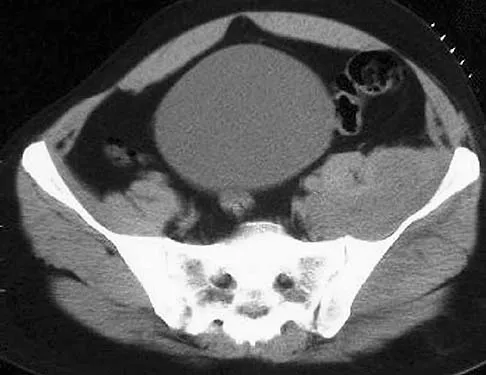

A 42-year-old patient has had a fever and low back pain for several days. Laboratory studies show an elevated erythrocyte sedimentation rate and a WBC count of 9,500 mm3 with 75% neutrophils. A CT scan is shown in Figure 15. Examination will most likely reveal what other findings?

Explanation